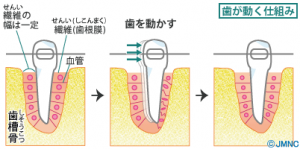

歯が動く仕組み